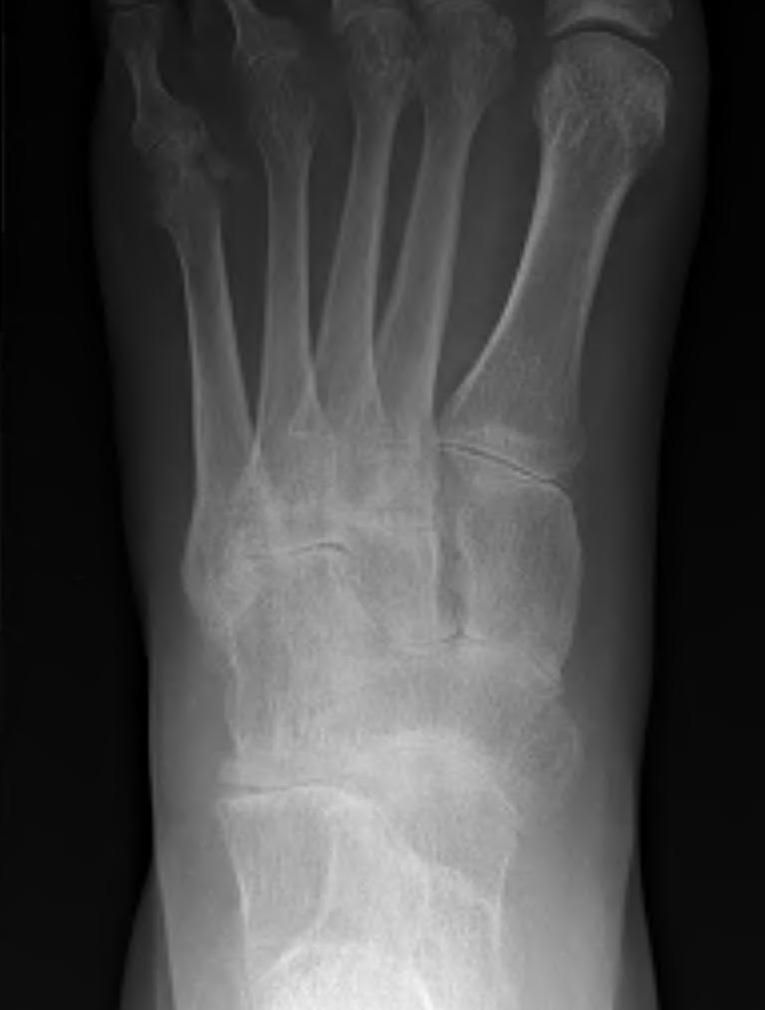

Metatarsalgia

Pathology

Synovitis of MTPJ with capsular destruction

- dorsal subluxation MTPJ

- claw toes develop (MTPJ hyperextended, PIPJ flexed)

- plantar fat pad displaced distally and metatarsal heads exposed to plantar skin